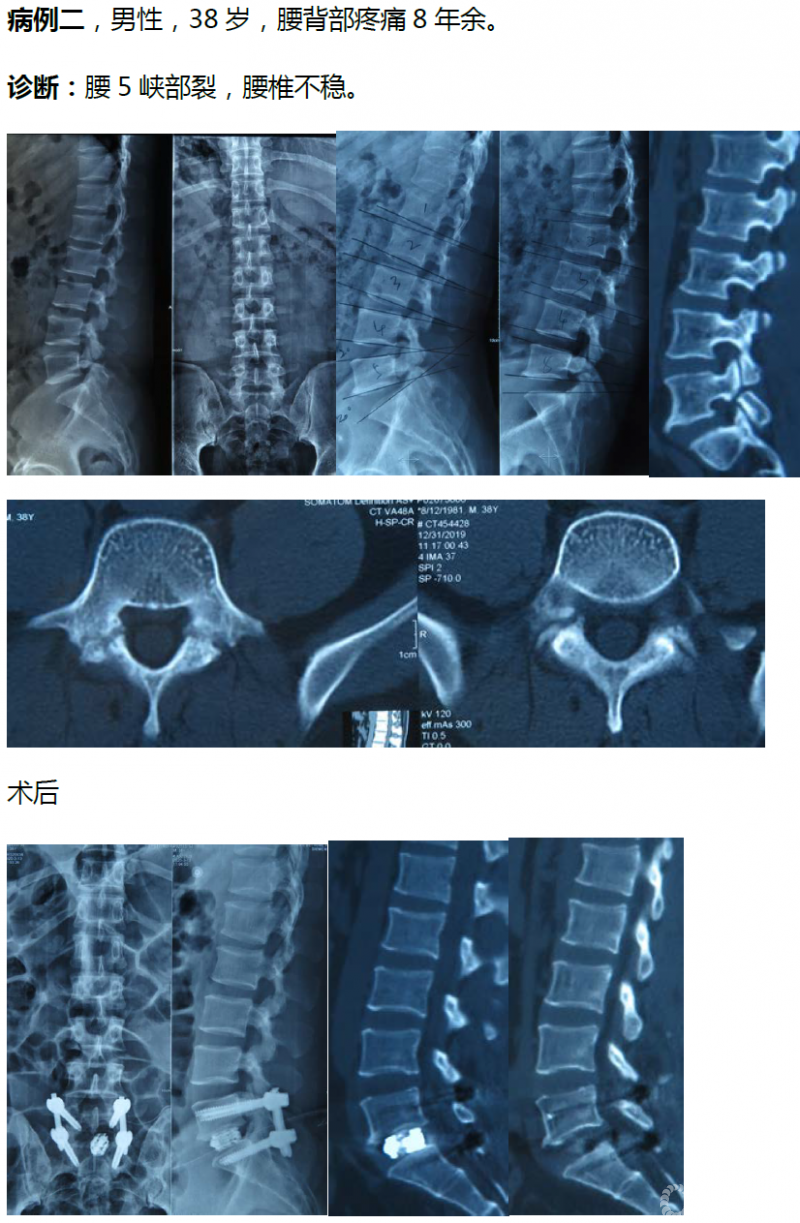

病例分享:(滑动查看)